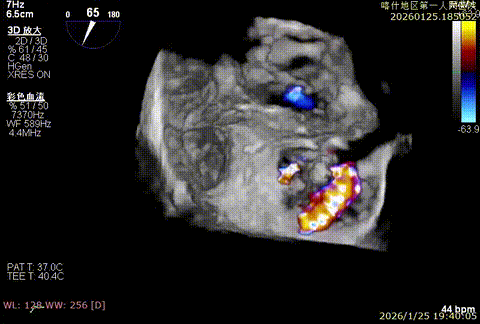

该例患者为VFMR,术前制定手术策略:患者二尖瓣重度反流,后叶严重栓系,心房心室扩大。患者瓣口面积4.5cm2,预计使用两枚XTR解决患者瓣叶脱垂和反流。考虑到先于2区进行钳夹,应该能获得足够的房间隔穿刺高度。术中经不断调整穿刺位点,最终穿刺高度4.4cm。成功穿刺后将第一枚XTR送入二尖瓣正上方,进行弹道测试Orientation调整后,最终定位于2区正上方下左心室。第一枚夹子在左室成功捕捞和钳夹瓣叶后,瓣叶反流程度显著降低,夹子外侧仍见部分反流,随后在第一枚夹子外侧再次放置一枚XTR,瓣叶反流程度进一步降低至微量。通过TEE观察,二尖瓣双孔组织桥稳定,跨瓣压差3mmHg,肺静脉逆流改善明显,手术安全结束。

X-plan重度反流

3D enface后叶栓系

3D enface观察反流